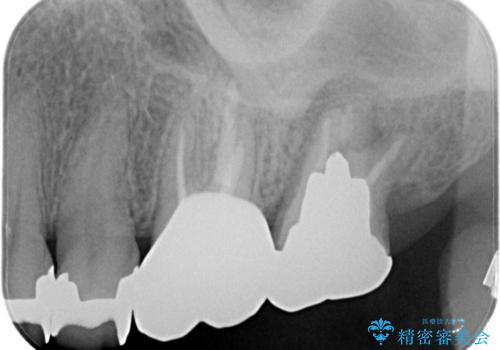

【根管治療】未処置根管を有した歯の再根管治療

- 定期検診にて虫歯を見つけたため、根管治療からオールセラミッククラウンによる修復治療を行いました。

レントゲンにて透過像を認めている上顎第二大臼歯も治療予定です。

上顎第一大臼歯の近心根にはほとんどの場合、神経の管が二本あることが多いです。顕微鏡を用いることで見逃すことなく治療が行えました。